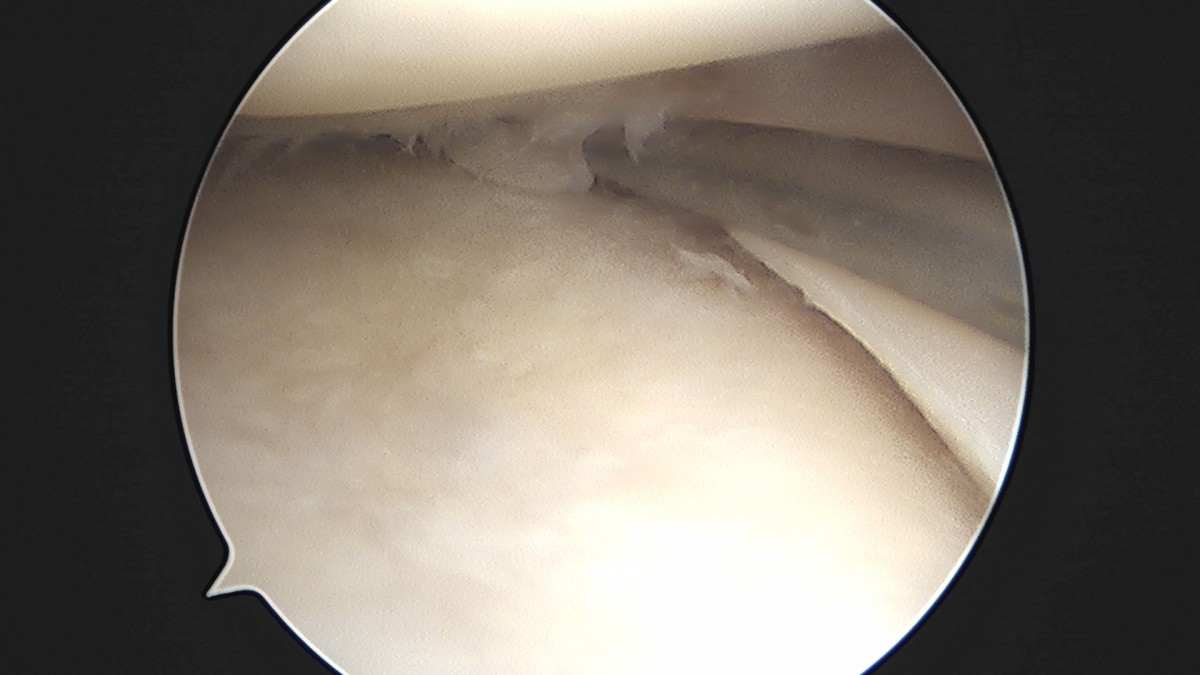

이재상원장님 무릎 반월상 연골판 절제술 고기O 환자

dae765e4d9ac96aee867c9d6292d8784_1758005092_9008.jpg